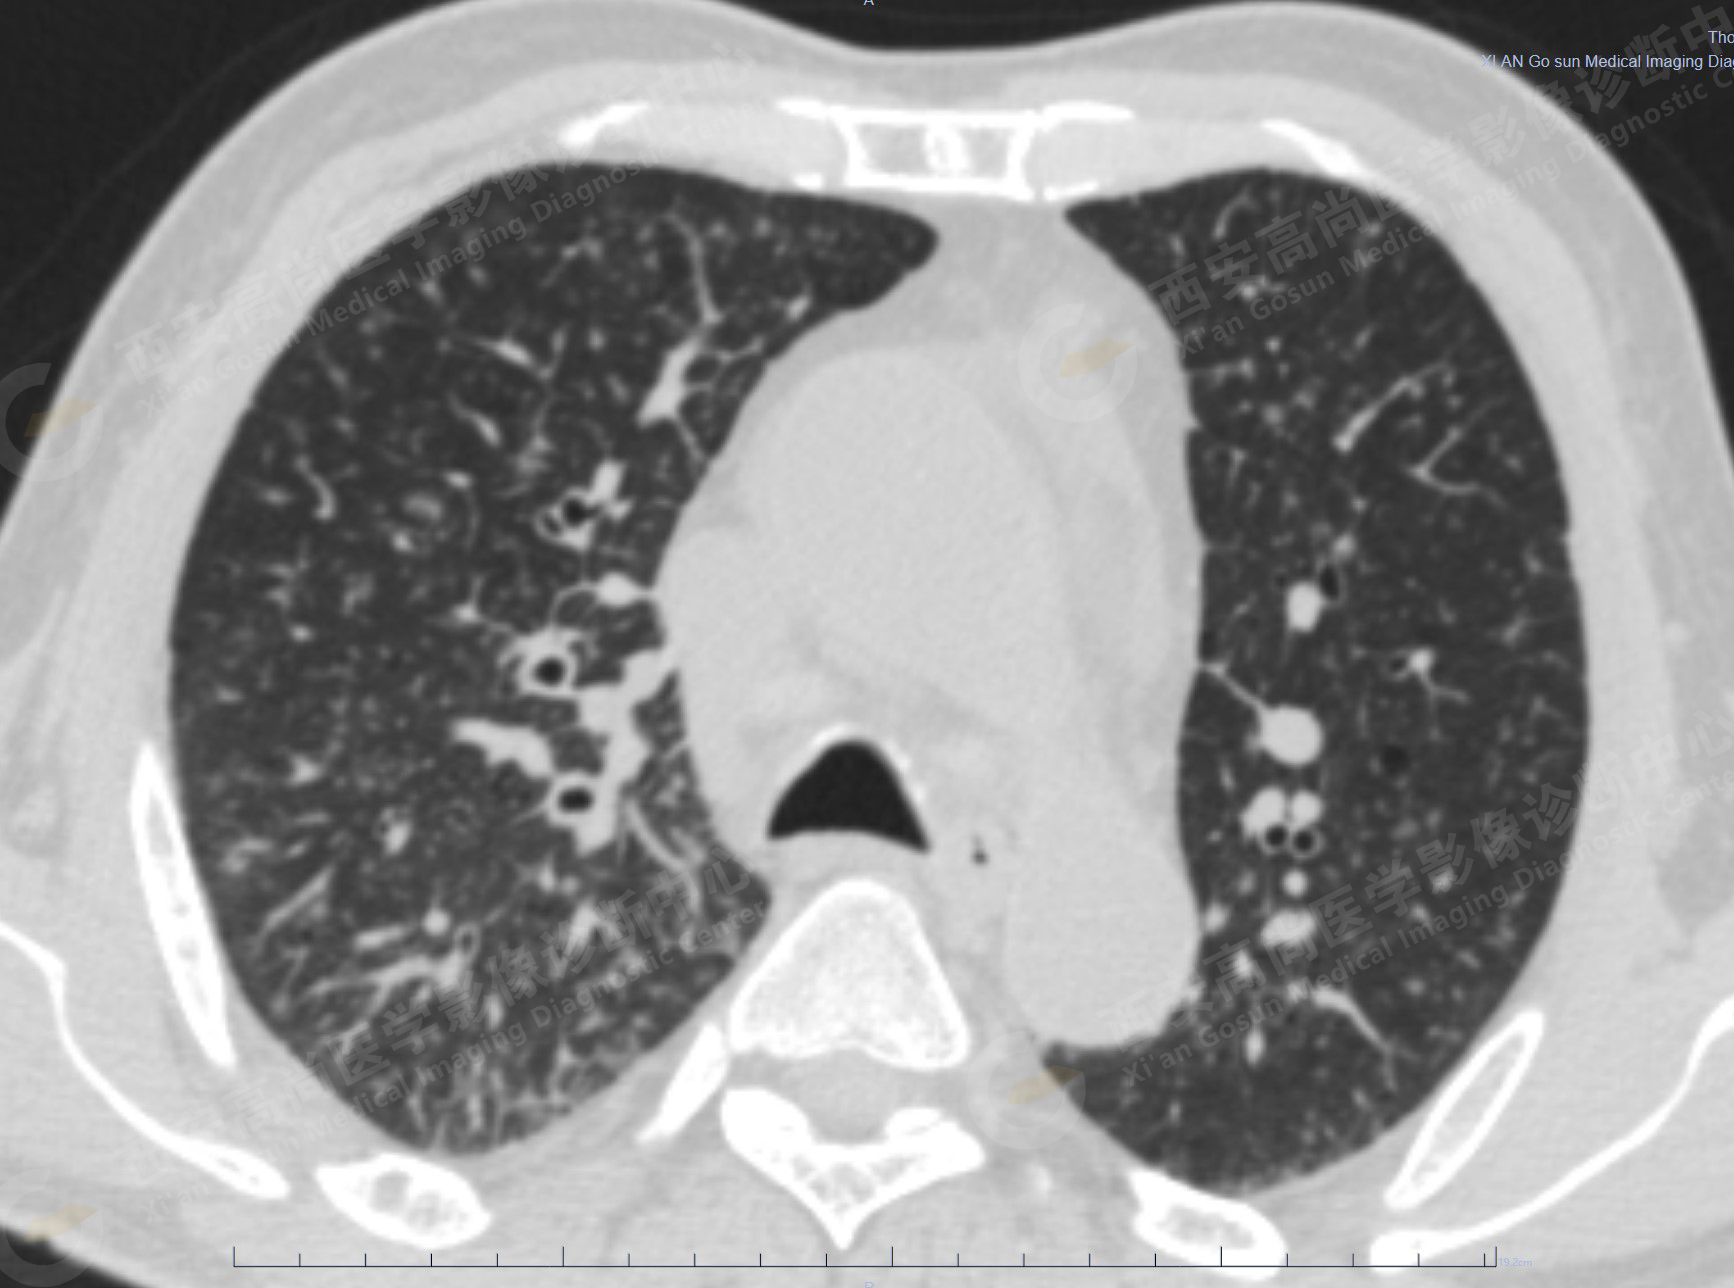

2.雙肺內(nèi)彌漫性分布大小不等實性小結節(jié)灶及粟粒狀高密度影,均未見FDG代謝明顯異常增高,均多考慮為癌性淋巴結炎及轉移性病變。